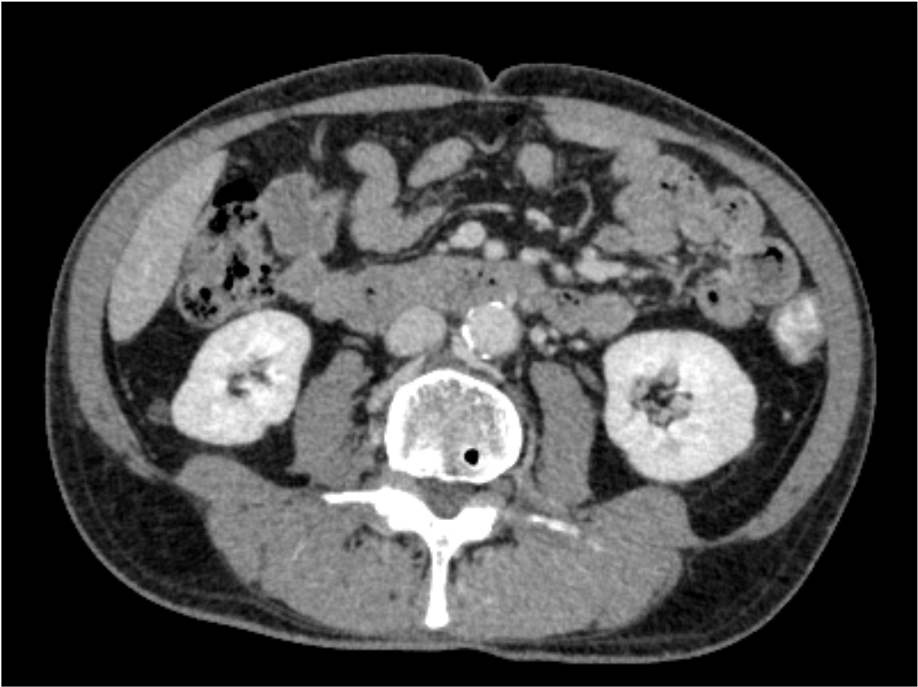

数日来の血便あり。臨床的に憩室出血が疑われCT検査が施行された。造影CTにて、下行結腸の憩室より造影剤の漏出像を認め、活動性出血と考えられた。下部消化管内視鏡でも下行結腸の憩室より噴出性の出血が確認され、憩室出血の診断。クリップにて止血処置を行い、止血が確認された。

当該疾患の診断における造影CTの役割